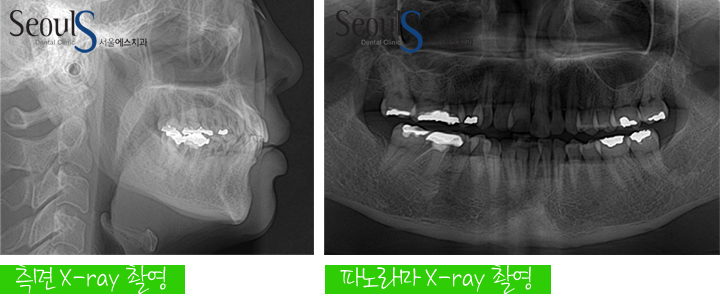

교정 진단과정

측면 X-ray 촬영, 파노라마 X-ray 촬영, 진단 모형 제작 및 3차원 분석 후

컴퓨터 교정 프로그램에 입력해 진단합니다

진단내용

이번 증례의 경우 삐뚠 치아를 이동하기 위해서 공간이 필요했는데

공간 부족량이 비교적 적기 때문에

치아 사이를 다듬어 공간을 만들고 치열을 개선하기로 계획했습니다